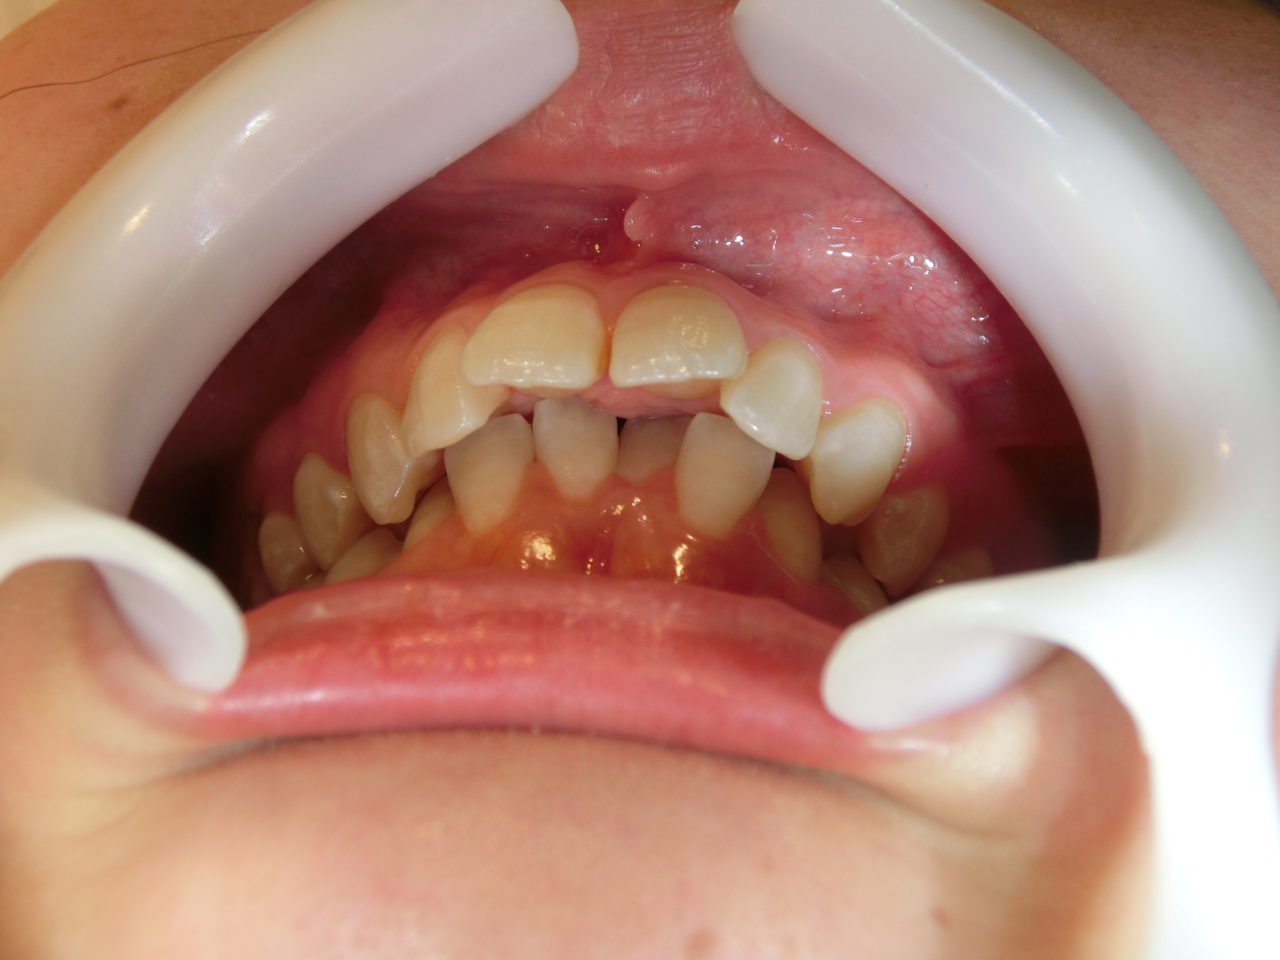

出っ歯の矯正(上顎前突)

【出っ歯とは】

上の前歯や上あごが前に出ている状態を「出っ歯(上顎前突)」といいます。

「口が閉じにくい」「前歯で物が咬みにくい」「横顔のバランスが気になる」など、

見た目だけでなく機能面でもさまざまな影響があります。

【主な原因】

・上あごの骨格が前に出ている

・前歯が前方へ傾いている

・指しゃぶりや舌の押し出し癖

・遺伝的な要因

歯だけでなく骨格的な要素も関係しているため、

正確な診断が大切です。